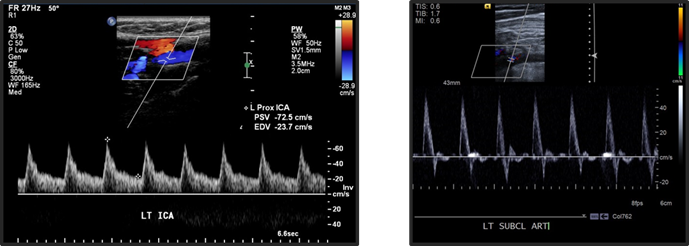

Resistive Index equation

RI = (PSV - EDV)/PSV

higher diastolic flow is seen in what arteries?

carotid and vertebral artries (lower resistance waveforms –> lower RI)

lower diastolic flow is seen in what vessels?

extremities

lower diastolic flow = higher resistance waveform (higher RI)

due to elastic recoil.

retrograde flow may be seen in early diastole (triphasic flow)